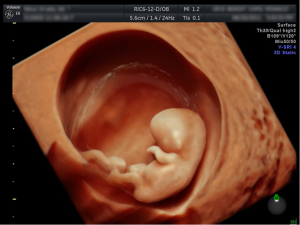

Ecografía 3D y 4D

constituye la última novedad en servicios de ecografías. Nos permite obtener impresionantes imágenes con un extraordinario realismo. Las ecografías en alta resolución brindan una claridad de imagen con un realismo único. Esta innovadora herramienta permite la posibilidad de integrar el volumen (3D) con una fuente de luz que ayuda a aumentar la percepción de profundidad, revelar detalles ocultos y proporcionar un conocimiento más profundo de la anatomía de su bebé y en tiempo real (4D)